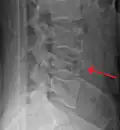

A burst fracture of L4 as seen one plane X ray -